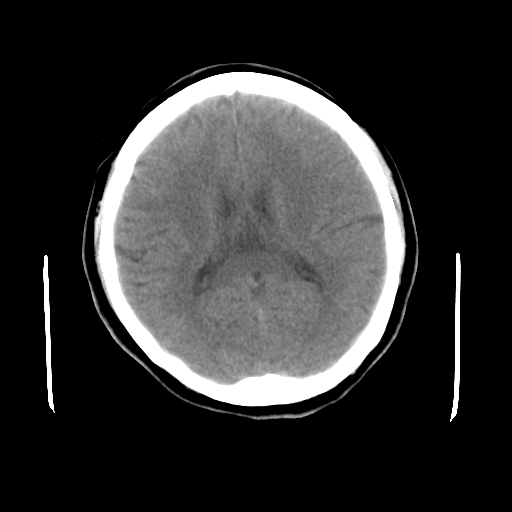

标题: CT23995:女,42岁,前额部外伤1小时,伤后头痛。 [打印本页]

女,42岁,前额部外伤1小时,伤后头痛。

头颅ct平扫未见异常

未见明显异常!

颅脑ct平扫未见异常,必要时复查

未见明显外伤性改变。

未见明显异常